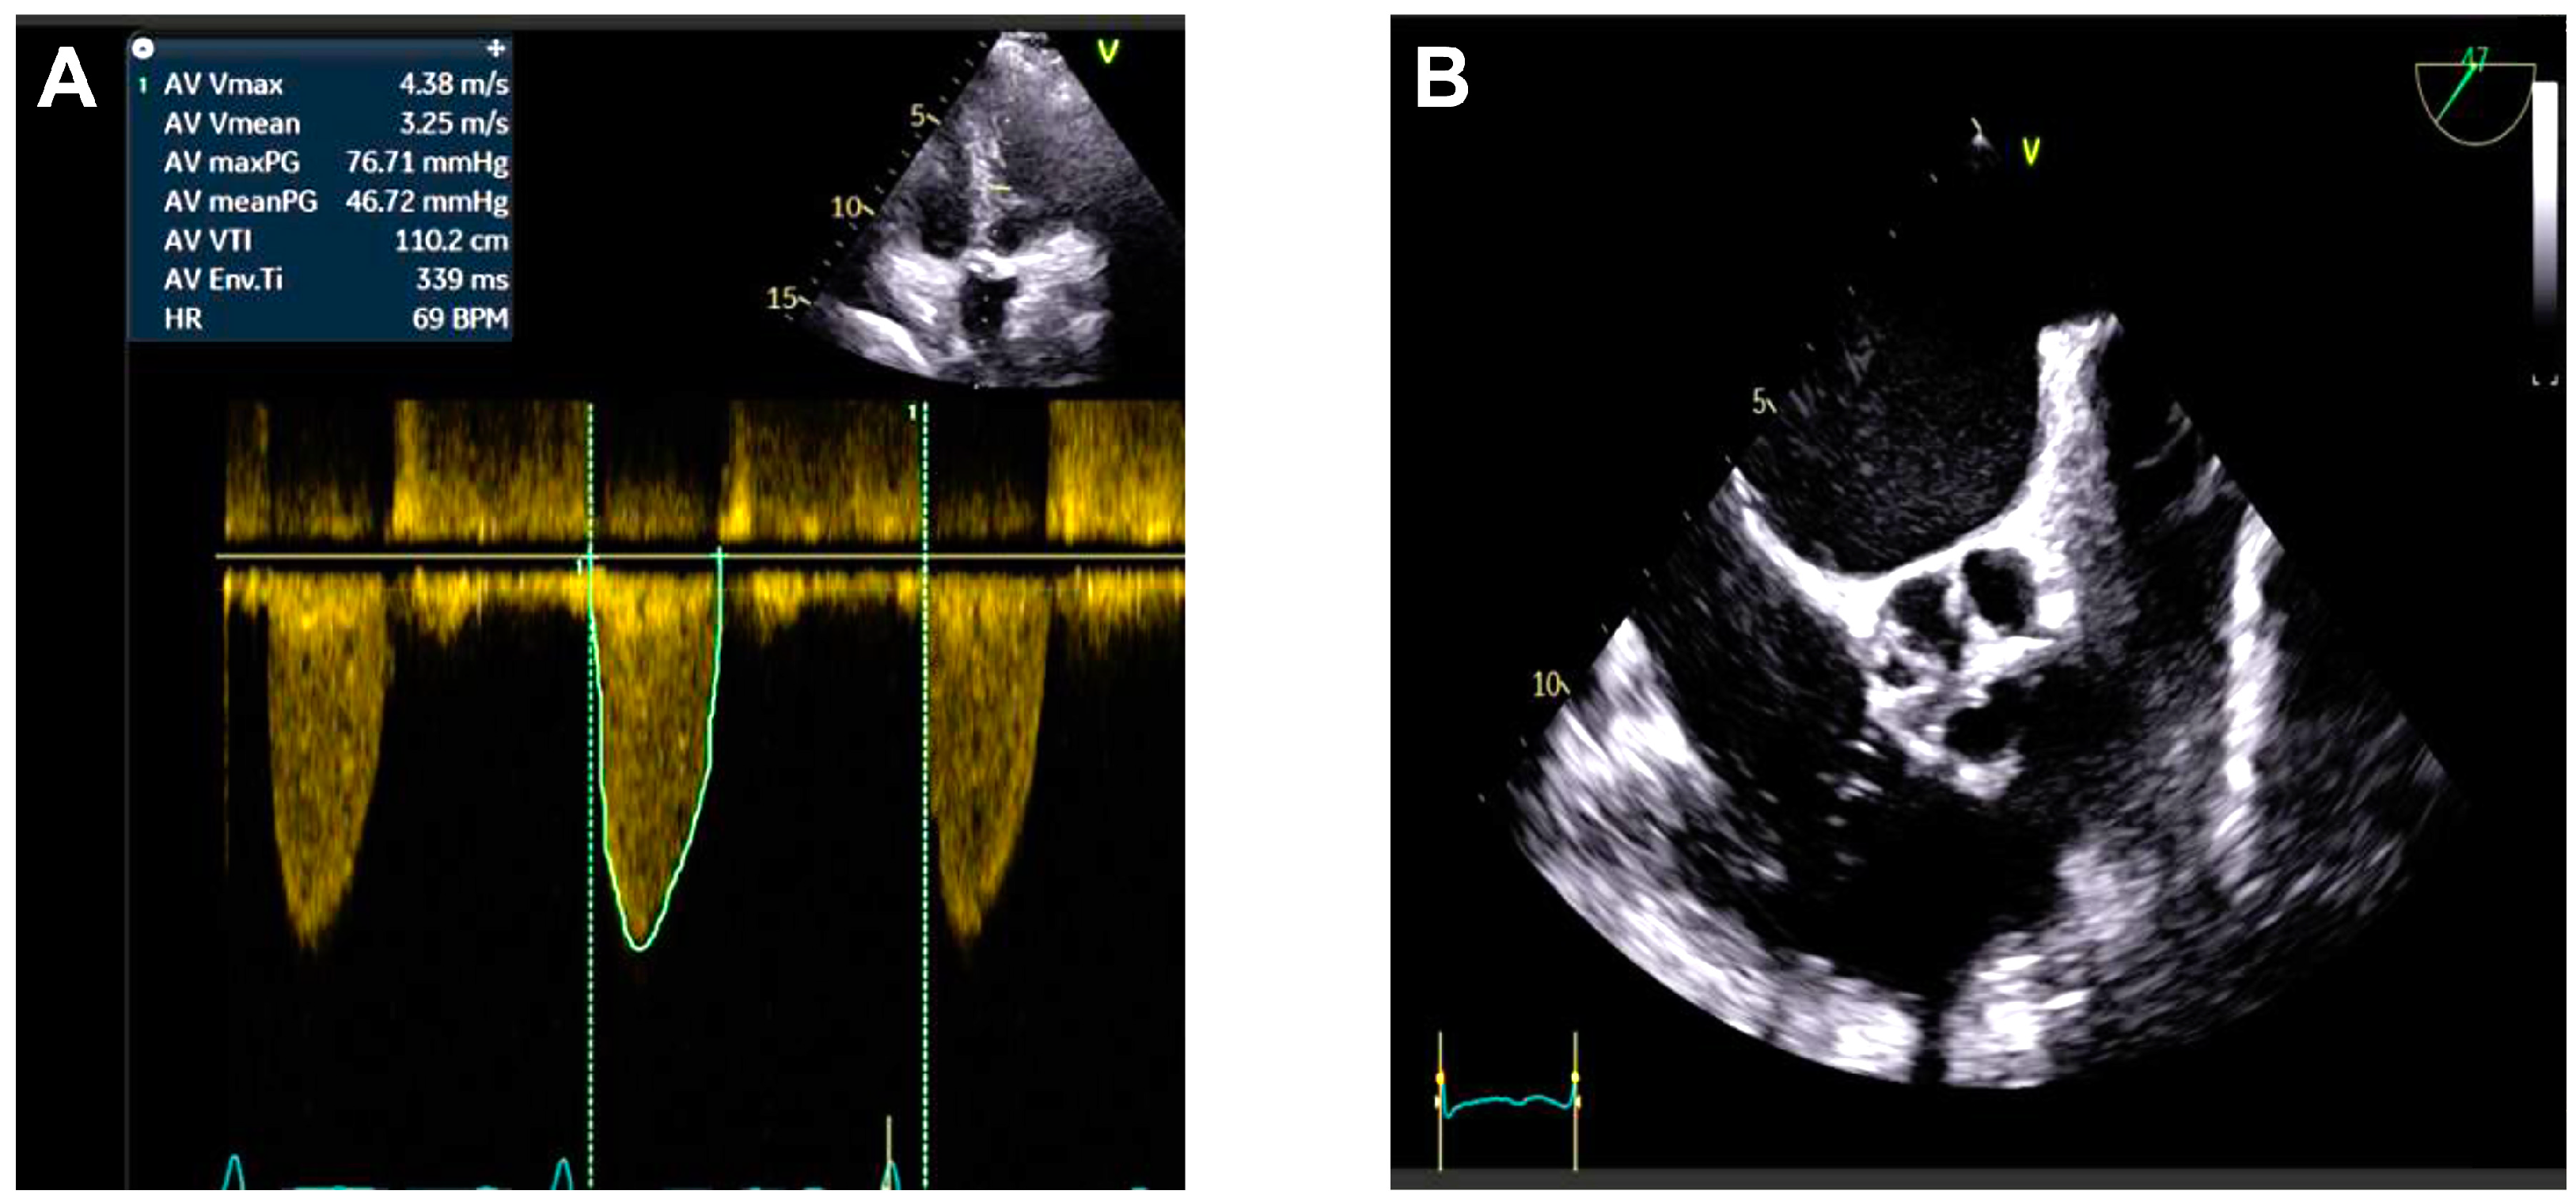

2. Case Presentation